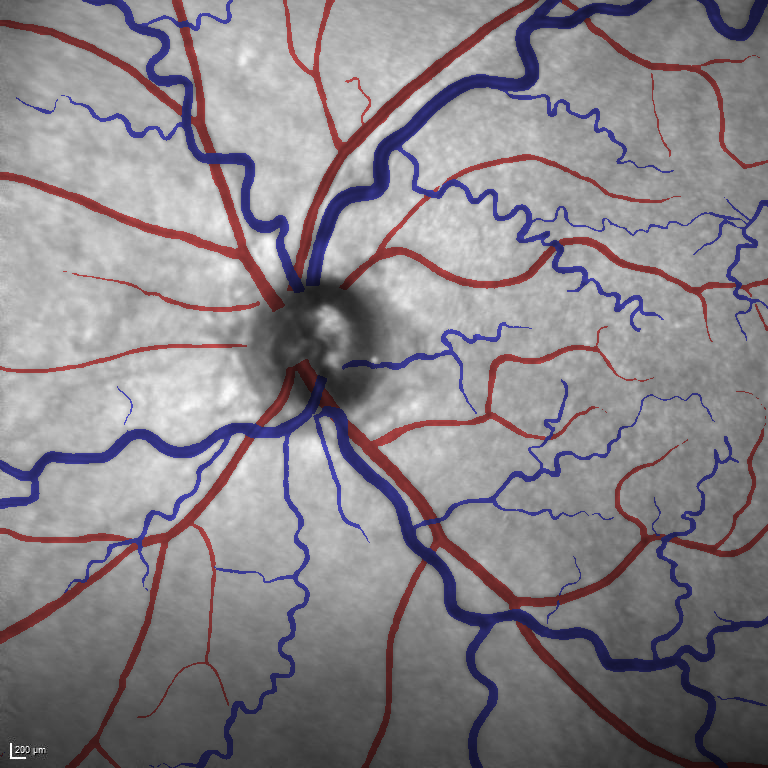

(a) Reference (b) Output (c) Width Map

As reported in Table IV, we compared the SegRAVIR model against competing deep learning-based segmentation approaches on the RAVIR dataset. Evidently, SegRAVIR outperforms these methods as judged by all metrics for artery and vein classes with a healthy margin. In terms of Dice score, SegRAVIR outperforms CE-NET, IterNet and AG-Net by , and for artery segmentation and by , and for vein segmentation, respectively. Fig. 4 presents a qualitative comparison of the semantic segmentation outputs of SegRAVIR, CE-Net, and U-Net. Specifically, SegRAVIR yields more accurate vessel topology (i.e., thickness and orientation) segmentation with higher pixel-wise classification accuracy.